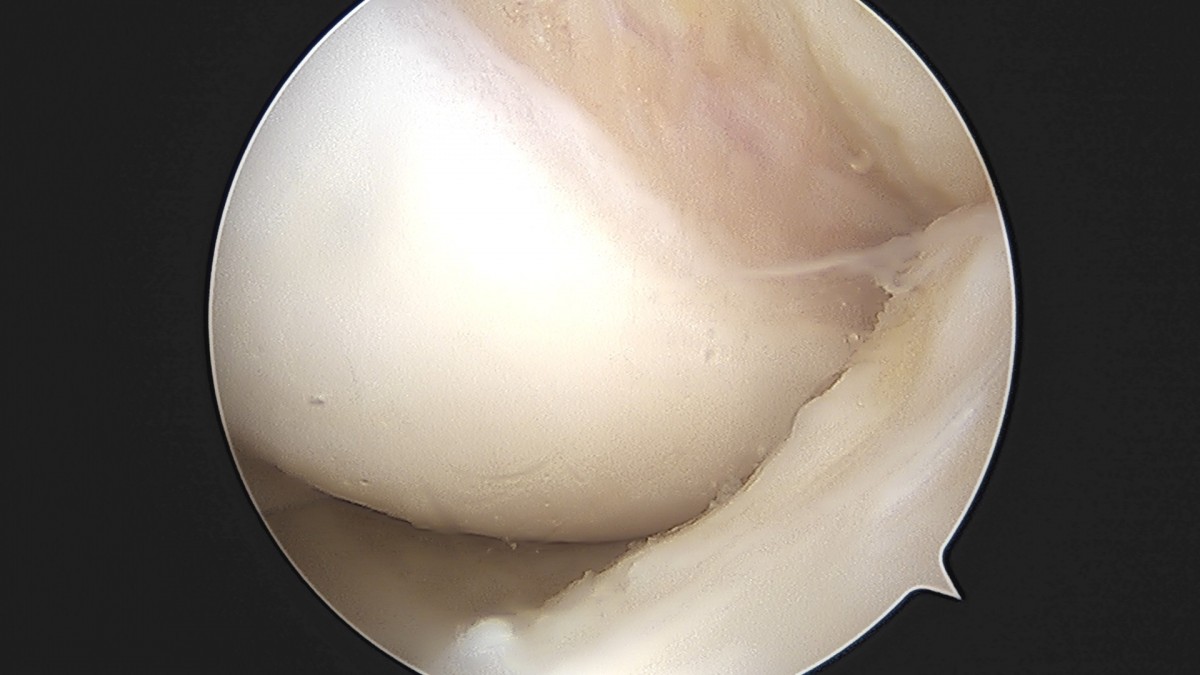

이재상원장님 무릎 낭종 제거술 김은O 환자

작성자 최고관리자 댓글 0건 조회 789회 작성일 25-09-16 15:20